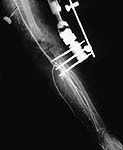

Case 1 - comminuted open supracondylar fx femur, no pulses, huge hematoma and bleeding. The angio shows popliteal artery transection. Immediately taken to OR where proximal and distal control are obtained prior to shunting. THEN Ortho ex-fixes the joint. The artery is definitively repaired. The wound is debrided. Later Ortho does a definitive ORIF with bone graft - successful.

Initial Angio

Transection Injury

Shunt